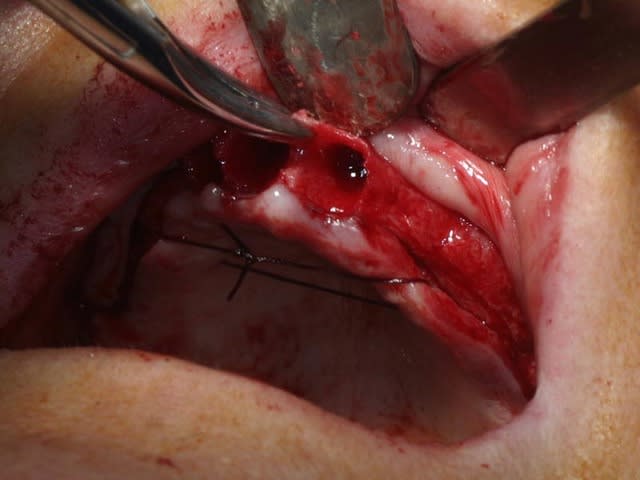

bon, toujours aussi speed je suis, mais après certaines réclamations, et malgrès ma réticence à poser un cas non "consolidé", voici en avant première mon premier all on 4, version photos ratées et non retouchées, mais... speed je suis je vous disais ;)

sto le bla bla, et pasons le diaporama... bon voyage au pays de la mise en charge immédiate totale au maxillaire de fille carole sur dame ginette, une patiente en or que j' adore, et pour qui je suis très très heureuse d' avoir pu réaliser cette chirurgie et la première étape prothétique.....

Tu as vraiment bien réussi à longer le plancher sinusal et apparemment la patiente pourra se pendre aux implants...